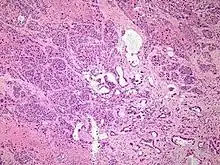

Micrograph of pancreatic ductal adenocarcinoma (the most common type of pancreatic cancer). H&E stain

Micrographs of normal pancreas, pancreatic intraepithelial neoplasia (precursors to pancreatic carcinoma) and pancreatic carcinoma. H&E stain

Histopathology

The most common form of pancreatic cancer (adenocarcinoma) is typically characterized by moderately to poorly differentiated glandular structures on microscopic examination. There is typically considerable desmoplasia or formation of a dense fibrous stroma or structural tissue consisting of a range of cell types (including myofibroblasts, macrophages, lymphocytes and mast cells) and deposited material (such as type I collagen and hyaluronic acid). This creates a tumor microenvironment that is short of blood vessels (hypovascular) and so of oxygen (tumor hypoxia).[11] It is thought that this prevents many chemotherapy drugs from reaching the tumor, as one factor making the cancer especially hard to treat.[11][3]